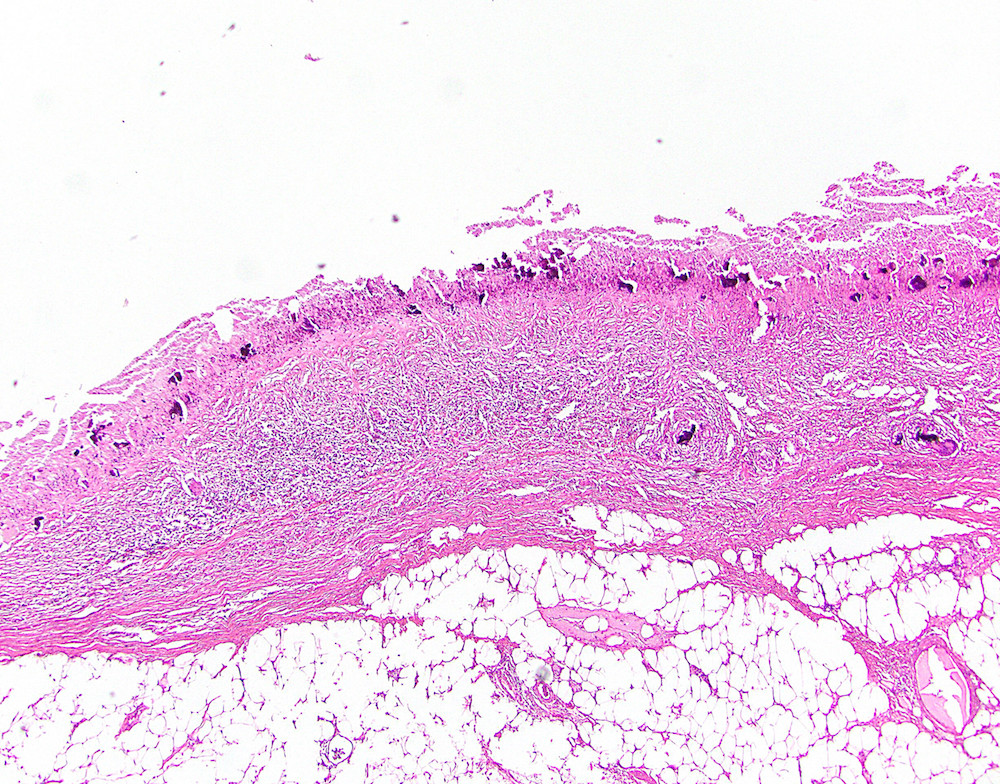

Microscopic (histologic) description

- Villous or occasionally flat proliferation of mucinous epithelial cells originating from appendiceal lumen

- Lesional cells typically demonstrate abundant apical mucin with elongated nuclei and low grade nuclear atypia (LAMN); however, nuclei may appear compressed or rarely high grade (HAMN)

- Often associated with atrophy of underlying lymphoid tissue, crypt loss and effacement of muscularis mucosae

- Broad dissection of mucin, epithelium or both may occur with potential involvement of extra-appendiceal surface, an important finding affecting prognosis

- Extra-appendiceal mucin incites a serosal reaction and may contain neovascularization, assisting in differentiation from benign transfer of mucin during gross examination

Microscopic (histologic) images

Contributed by Raul S. Gonzalez, M.D. and Michael Feely, D.O.